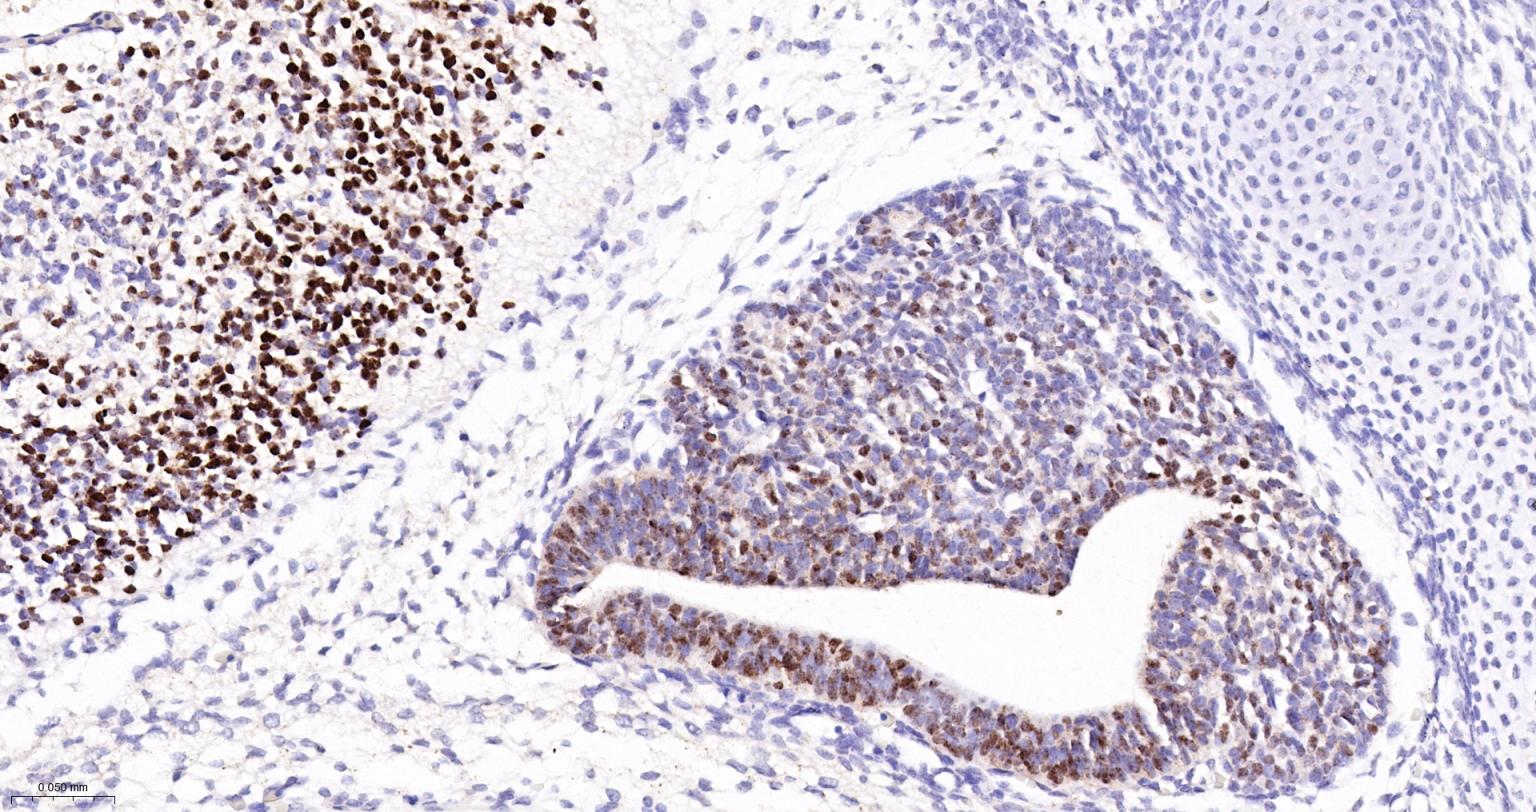

Paraformaldehyde-fixed, paraffin embedded Human Esophagus Cancer; Antigen retrieval by boiling in sodium citrate buffer (pH6.0) for 15 min; Antibody incubation with SOX2 Monoclonal Antibody, Unconjugated(bsm-60788R) at 1:300 overnight at 4°C, followed by conjugation to the SP Kit (Rabbit, SP-0023) and DAB (C-0010) staining.